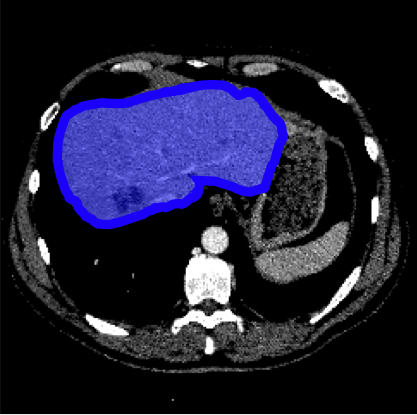

Consider a three-dimensional object within a volume. It is straightforward to produce a 3D bounding box of the object by finding its extreme points in the three coordinate axes. While this 3D bounding box will be tight in the 3D sense, its rectangular cross-sections will not, in general, remain tight with respect to the planar cross-sections of the volume. Fig. 1 illustrates such a case for the task of liver segmentation in a CT volume. In the Experiments section we show that the success of existing 2D weakly-supervised segmentation methods relies on the bounding boxes being tight and therefore the tightness of the individual 2D bounding boxes should be corrected before training and applying a segmentation CNN.

The global bounding box tightness prior mentioned above assumes that each of side of the box is sufficiently close to the target region. This means that for any region shape, each vertical or horizontal line inside the bounding box will cross at least one pixel belonging to the target region. This condition does not hold when the provided annotation comes as a 3D bounding box which is represented as a series of per-slice non-tight 2D bounding boxes. In this case, there will exist vertical or horizontal lines shown as stripes in Fig. 1 (d), that will lie outside of the actual object boundary. In the Experiments section we demonstrate the poor performance of the weakly-supervised approach from [5] when the user-provided bounding box is much wider than the true object of interest.